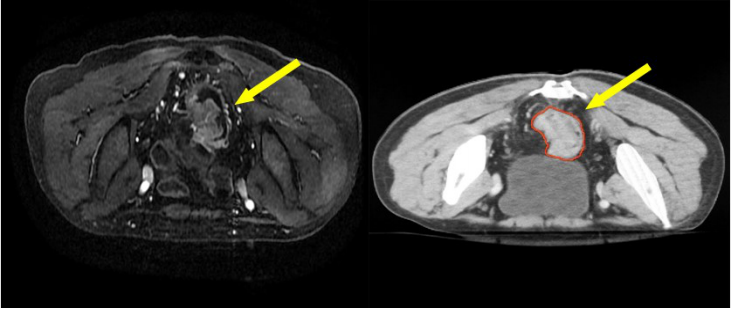

• 直肠癌的三维放疗及调强放疗靶区勾画

直肠癌的三维放疗及调强放疗靶区勾画

直肠癌是中国常见和高发疾病,好发于 40 岁以上人群。大部分直肠癌是散发病例,也可能源于某些遗传病,但仅约占 5%的病因。在西方国家是常见肿瘤,在中国发病率也逐年升高,其发病率和死亡率均排在前十位。散发性直肠癌的具体病因不明,主要与遗传因素、环境因素和生活方式有密切关系。

直肠癌的症状在早期通常不明显且无特异性,随着肿瘤进展常见的局部症状包括:大便习惯改变,